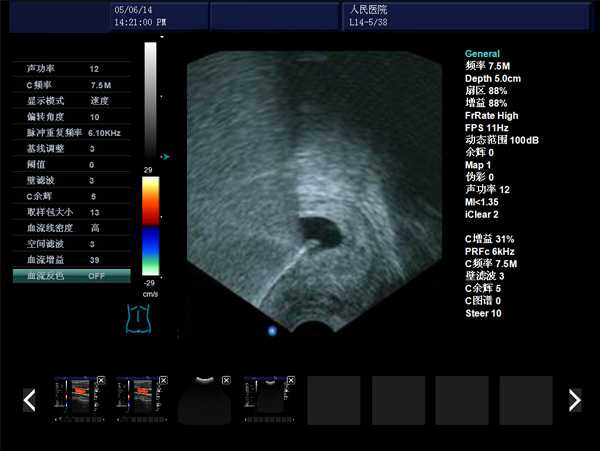

DW-480全數字超聲婦產科手術監視儀

DW-480

探頭與陰道窺器相結合,不進入宮腔,不占手術宮頸空間,手術更方便

實時動態高線密度超大角度掃描,有效提升橫向分辨力和側向分辨力、圖像自然更清晰

采用大容量電影回放,實時精微顯示等全數字圖像處理技術,宮腔內部圖像清晰可辨,不容錯過一點殘留,手術干凈徹底,避免了吸宮不全、漏吸等并發癥的發生